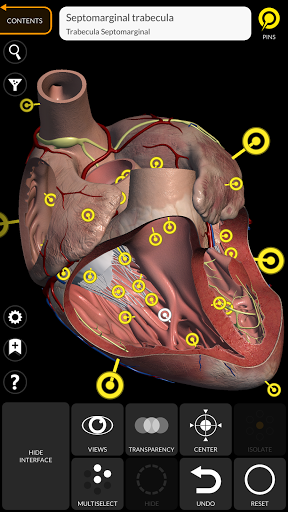

"Anatomy 3D Atlas" memungkinkan Anda mempelajari anatomi manusia dengan cara yang mudah dan interaktif.

Melalui antarmuka yang sederhana dan intuitif, Anda dapat mengamati setiap struktur anatomi dari sudut mana pun.

Model 3D anatomi sangat terperinci dan memiliki tekstur hingga resolusi 4k.

saraf • Sistem pernapasan • Sistem pencernaan • Sistem urogenital (pria dan wanita) • Sistem endokrin • Sistem limfatik • Sistem mata dan telinga FITUR • Antarmuka yang sederhana dan intuitif • Putar dan perbesar setiap model dalam ruang 3D • Opsi untuk menyembunyikan atau mengisolasi satu atau beberapa model yang dipilih • Filter untuk menyembunyikan atau menampilkan setiap sistem • Fungsi pencarian untuk menemukan setiap bagian anatomi dengan mudah • Fungsi penanda untuk menyimpan tampilan khusus • Rotasi cerdas yang menggerakkan pusat rotasi secara otomatis • Fungsi transparansi • Visualisasi otot melalui tingkat lapisan dari yang superfisial hingga yang terdalam • Dengan memilih model atau pin, istilah anatomi terkait akan muncul • Deskripsi otot: asal, • Tampilkan/ Sembunyikan antarmuka UI (sangat berguna dengan layar kecil) MULTIBAHASA • Istilah anatomi dan antarmuka pengguna tersedia dalam 11 bahasa: Latin, Inggris, Prancis, Jerman, Italia, Portugis, Turki, Rusia, Spanyol, Mandarin, Jepang, dan Korea • Istilah anatomi dapat ditampilkan dalam dua bahasa secara bersamaan PERSYARATAN SISTEM • Android 8.0 atau yang lebih baru, perangkat dengan RAM minimal 3GB Reversi